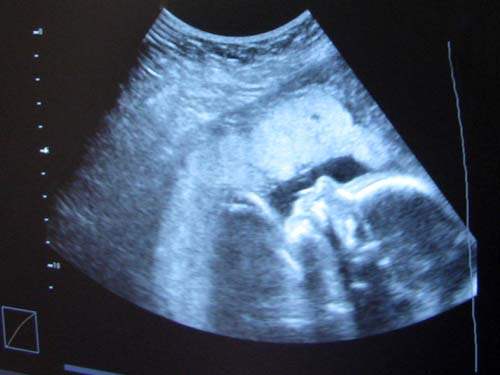

Amniyon kesesinin içi, amniyon sıvısı denilen bir sıvı ile doludur. Bu sıvının miktarı son derece önemlidir. Çünkü yetersizliği durumunda bebeğin gelişiminde önemli sorunlara yol açabilir. Bu yüzden her ultrason kontrolünde bebeğin kilosunun ardından, amniyon sıvısı ölçümü de yapılmaktadır. Aynı şekilde amniyon sıvısının çok olması da bir takım sorunlara işaret edebilmektedir. Bu nedenle ölçümün yapılması önemlidir.

Amniyon sıvısının az olması böbreklerinin az çalıştığının işareti olabileceği gibi, gelişiminin iyi gitmediğine de işaret edebilir. Çünkü gelişiminde sorun olan bebeğin ilk yapacağı şeyler, hareketlerini ve idrarını kısıtlamak olacaktır. Amniyon sıvısının fazlalığı ise, öncelikle üretimde yani idrarda bir fazlalık olduğuna işaret eder. Eğer annede şeker varsa, bu bebeğe de geçmiş ve idrarını artırmış olabilmektedir. İkinci olarak ise, bebeğin yutmasıyla ilgili bir sorun olduğuna işaret edebilir. Amniyon sıvısının azalması her zaman ciddi bir durumdur. Ancak bir miktar artması her zaman bir olumsuzluk işareti değildir.